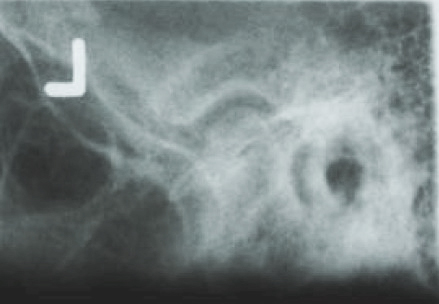

The transcranial view does not project a true sagittal image of the condyle, fossa, or joint space. Because of the distortion that results from the angle of the x-ray beam to these joint structures, this projection has largely been abandoned in favor of more accurate and revealing projections. Historically, one of the advantages of the transcranial projections has been that it could be taken in the dental office.